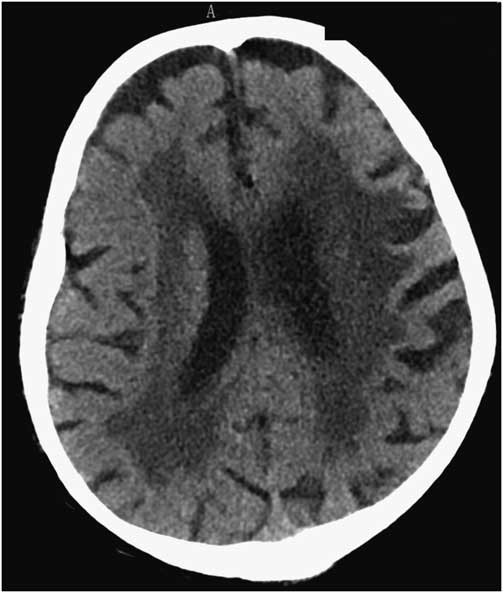

A 91-year-old man was admitted to our hospital with an acute right-sided hemiplegia and somnolence, which had appeared the day before. On admission, myoclonic jerks of the right hemibody were noticed, which promptly stopped after levetiracetam (1000 mg intravenous) administration. His medical history was notable for severe Alzheimer's disease (diagnosed 22 years earlier), chronic vascular encephalopathy with parkinsonism, moderate renal failure, and pancreatic carcinoma. The head CT scan showed ischemic lesions in the left hemisphere, more prominent in the fronto-parietal and temporal lobe, with marked chronic vascular encephalopathy and leukoaraiosis (Figures 1 and 2); the radiological features of the left temporal hypodensity were suggestive of a subacute cerebral infarction. The day after the admission, continuous involuntary contractions of the trunk were noted. Neurological examination showed continuous involuntary and rhythmic jerks involving the abdominal muscles, not spreading to other parts of the body (video). The electroencephalogram (EEG) (Figure 3) revealed rhythmic epileptiform discharges of triphasic/diphasic morphology admixed with polyspikes confined to the left hemisphere (Supplementary material). The most prominent epileptiform abnormalities were localized, over the left posterior temporo-parieto-occipital area. Equipotentiality of epileptiform discharges occurred between electrodes P3 and O1, sometimes with maximal amplitude over O1>P3≥T5>T3, C3 (more evident in referential montage). There were also independent epileptiform discharges located anteriorly, close to the anterior Sylvian region in the left fronto-temporal area, sometimes showing phase reversal at F7 or equipotentiality between F7 and T3. A periodicity (frequency of about 1 Hz) was sometimes evident in epileptiform discharges occurring in both posterior and anterior regions (i.e., lateralized periodic discharges). The EEG recording also showed brief ictal transitions seen maximally over the left posterior hemispheric structures, especially around T5. Overall, the EEG showed anterior and posterior areas of epileptogenicity, more marked in the left posterior temporo-parieto-occipital region. The myoclonic movements were not synchronous with the rhythmic epileptiform discharges. A concomitant electromyographic recording of the muscles of the abdominal wall showed bursts of quasirhythmic asymmetric polymorphic motor potentials of the right abdominal recti muscles, with a duration lower than 100 ms and a frequency of 0.5-1 Hz. The movements attenuated after intravenous administration of lorazepam (4 mg) and levetiracetam (2000 mg), but then reappeared. The patient died of cardiac arrest the following day.

Figure 1 Head CT scan showing marked chronic vascular encephalopathy and leukoaraiosis.